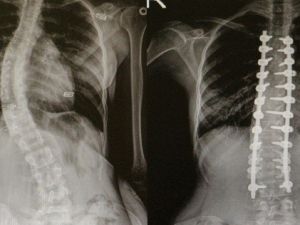

Omurga Eğriliği Olanlar Omü’de Şifa Buluyor